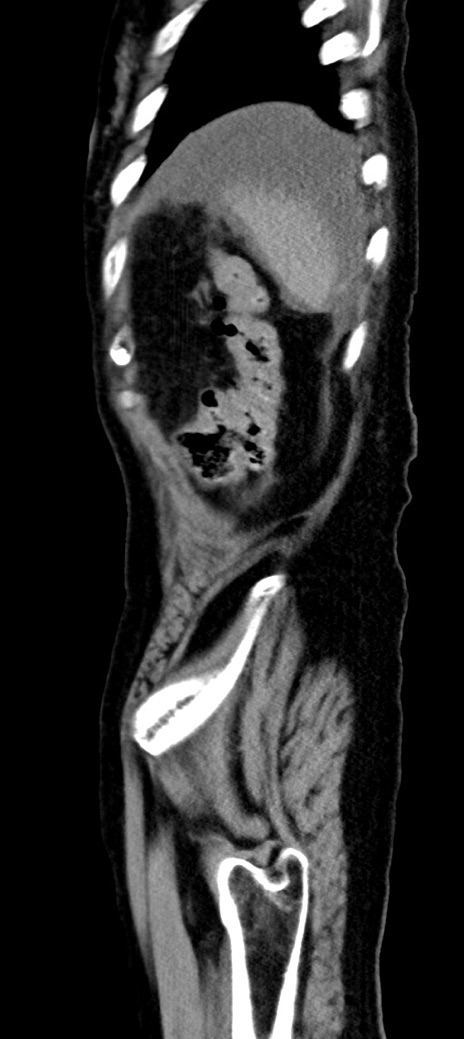

他院CT

横断像

冠状断像

【症例】90歳代女性

【主訴】腹痛・嘔吐

【現病歴】 食欲低下、嘔吐があり昨日他院受診。肺炎と診断され入院となる。入院後より腹部全体に圧痛あり。胃管留置され経過みていたが、症状持続するため、

当院転院となる。

【既往歴】胸椎圧迫骨折、胆石症

【身体所見】腹部:中央に激痛あり、圧痛あり、反跳痛不明

【データ】WBC 17100、CRP 18.82